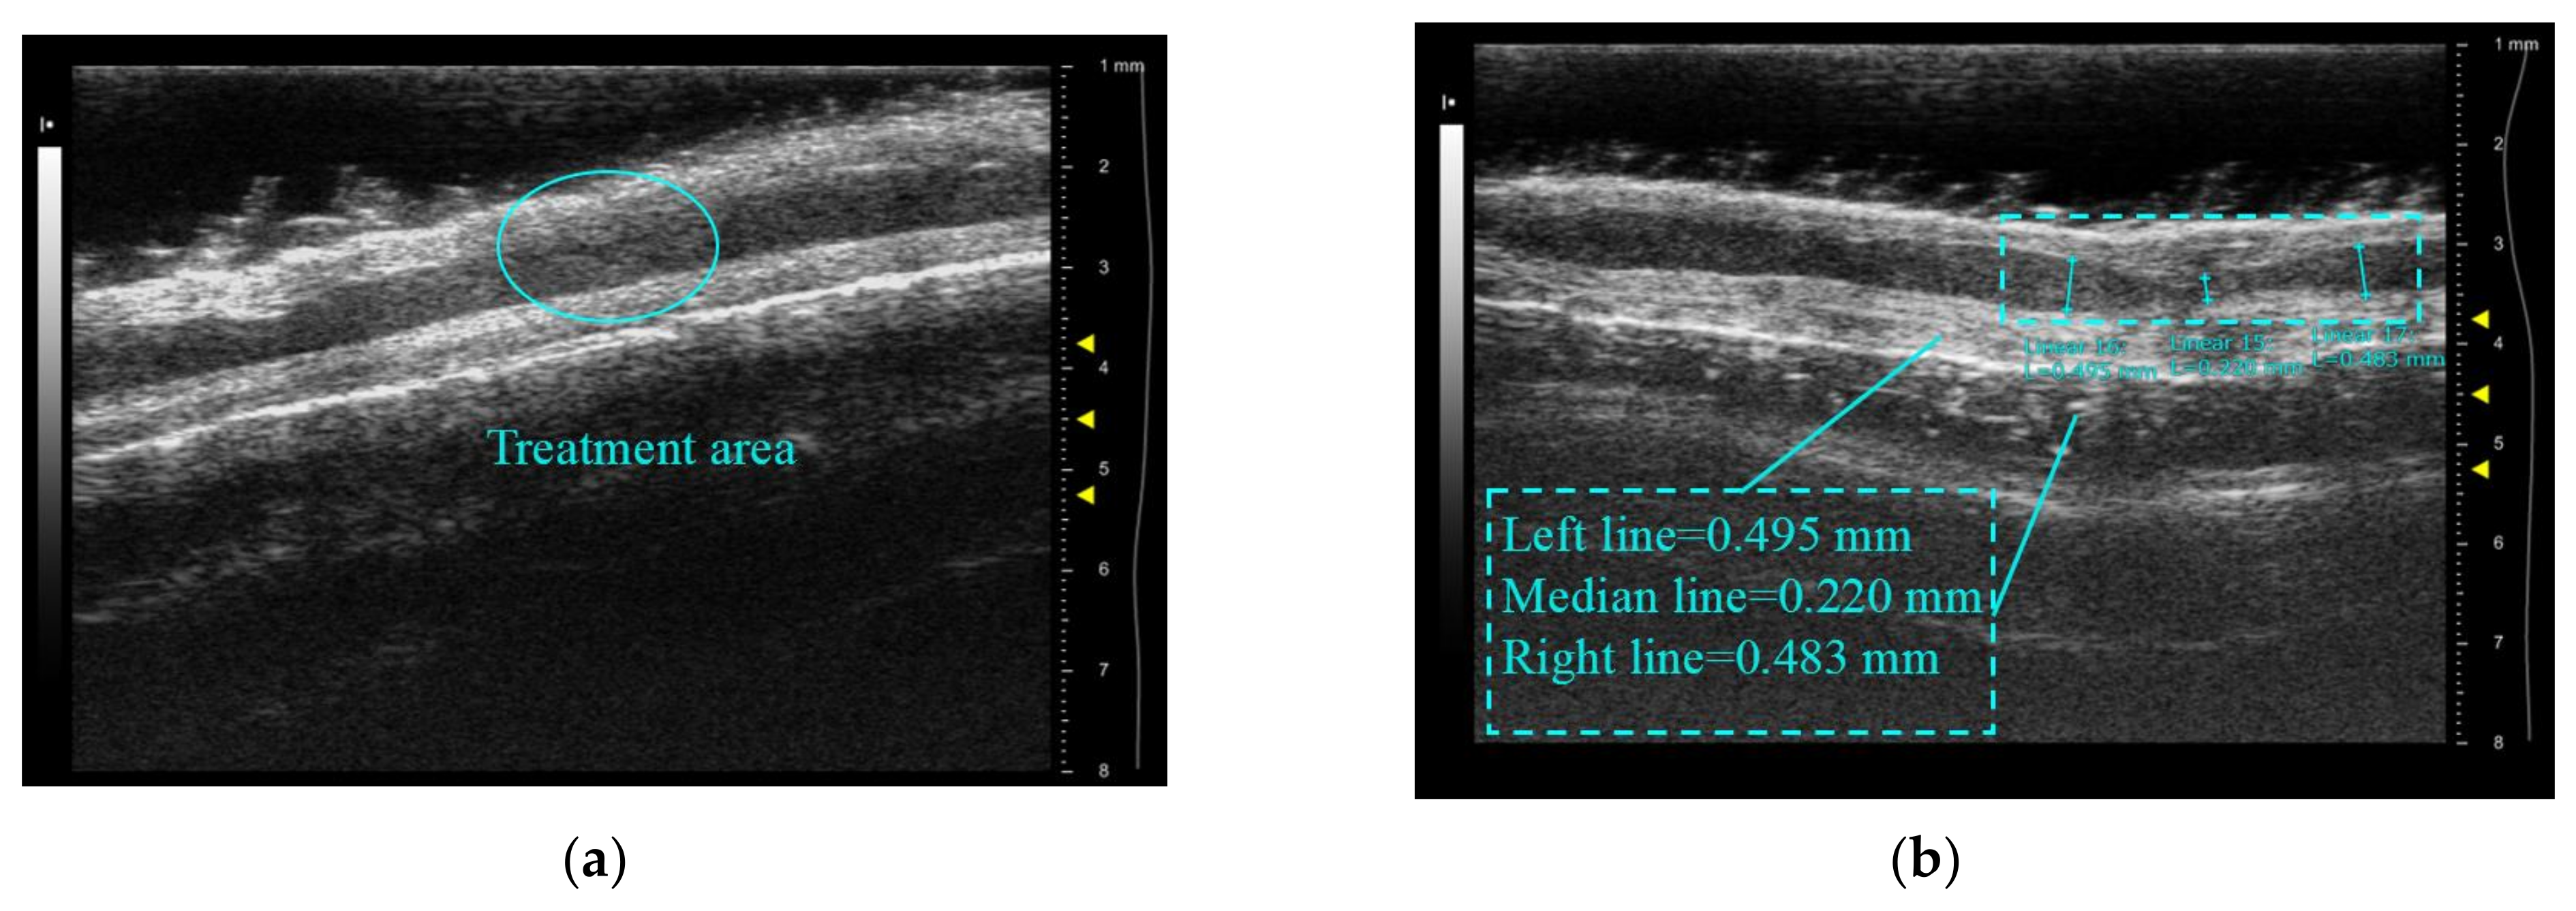

Figure 12a shows the ear margin vein of the rabbit to be treated after fur removal, and Figure 12b reveals that the skin in the treated area is in a white degeneration state compared with other areas in the path of the vein. This indicates that the treatment area is limited to the vascular area and does not cause burning of the surrounding tissue. The white degeneration state is believed to be a type of skin burn. Figure 13a displays an ultrasound image of the marginal ear vein in an untreated rabbit ear, while Figure 8b shows the same vein after treatment. Contraction and deformation of the blood vessel wall can be observed at the treatment point in Figure 13b. Furthermore, the internal diameters of the blood vessels were measured using the built-in measurement system of the Vevo 2100. The diameter of the untreated area was approximately 0.49 mm. After treatment, the blood vessel contracted to 0.22 mm, and the shrinkage rate was approximately 55%, which is consistent with the observed vascular degeneration results in Figure 12b. This confirms the accuracy of the treatment.

Figure 13.

The contrast image of rabbit ear vein contraction: (a) before treatment; (b) after treatment.

In in vitro validation experiments, due to the small size and slow blood flow speed of the rabbit ear margin veins compared to human veins, the temperature rises in the area quickly, and contraction of the superior and inferior vascular walls is observed. It is also found that if the treatment power is increased to pursue fast treatment, not only would the tissue and skin near the blood vessel be burned, but also the blood vessel would be directly ruptured and cause massive bleeding. Further research and consideration are needed to balance the treatment power and adopt appropriate cooling measures to protect the skin from burns.